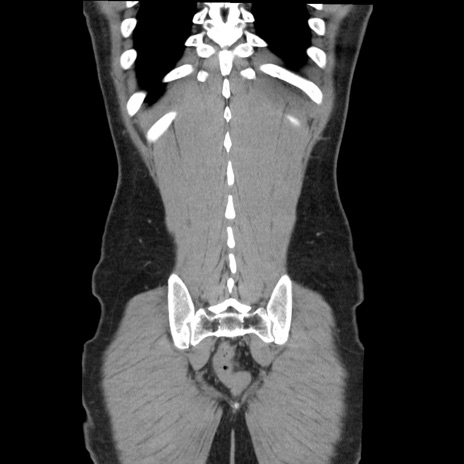

症例36(冠状断像)

【症例】20歳代 男性

【主訴】心窩部痛

【現病歴】今朝より上腹部痛あり。一旦軽快していたが再度出現したため救急要請。昨日夕に白身の魚を含む刺身を食べた。

【身体所見】BP 136/89mmHg、HR 74/min、BT 37.0℃、腹部:膨満、軟、心窩部に圧痛あり。反跳痛なし、筋性防御なし、腸雑音やや亢進あり。

【データ】WBC 17700、CRP 0.48